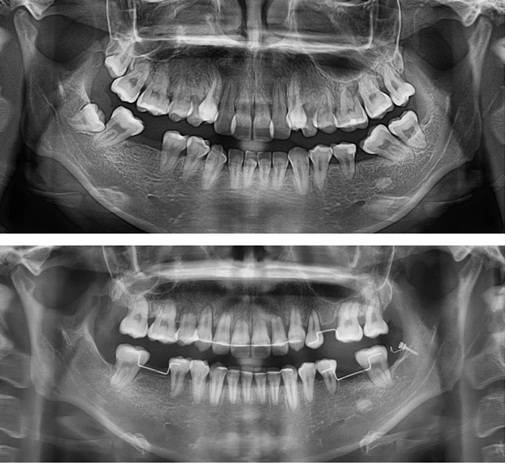

이 환자는 초진 시 턱관절 흡수 양상이 관찰된 경우입니다. 가운데 사진은 구강내과 치료 후 재진단 시행 시의 사진입니다. 아래 사진은 입술돌출 해소를 위해 발치교정을 시행하여 공간폐쇄를 거의 마무리 한 단계의 사진입니다. 이 환자에서 보듯이 초진 시 턱관절 질환이 있는 경우 하악은 매우 불안정한 위치에 있게 되고, 정확한 기준이 없으므로 정확한 치료계획을 세우기가 불가능합니다. 따라서 이런 환자는 구강내과적 치료를 통해 턱관절 위치를 안정화 시킨 후 치료계획을 수립해야 합니다. 그렇지 않고 바로 교정치료에 들어가는 경우 다음 내원 시 생각지 못한 위치로 이동해 있는 하악을 발견할 수도 있게 됩니다.